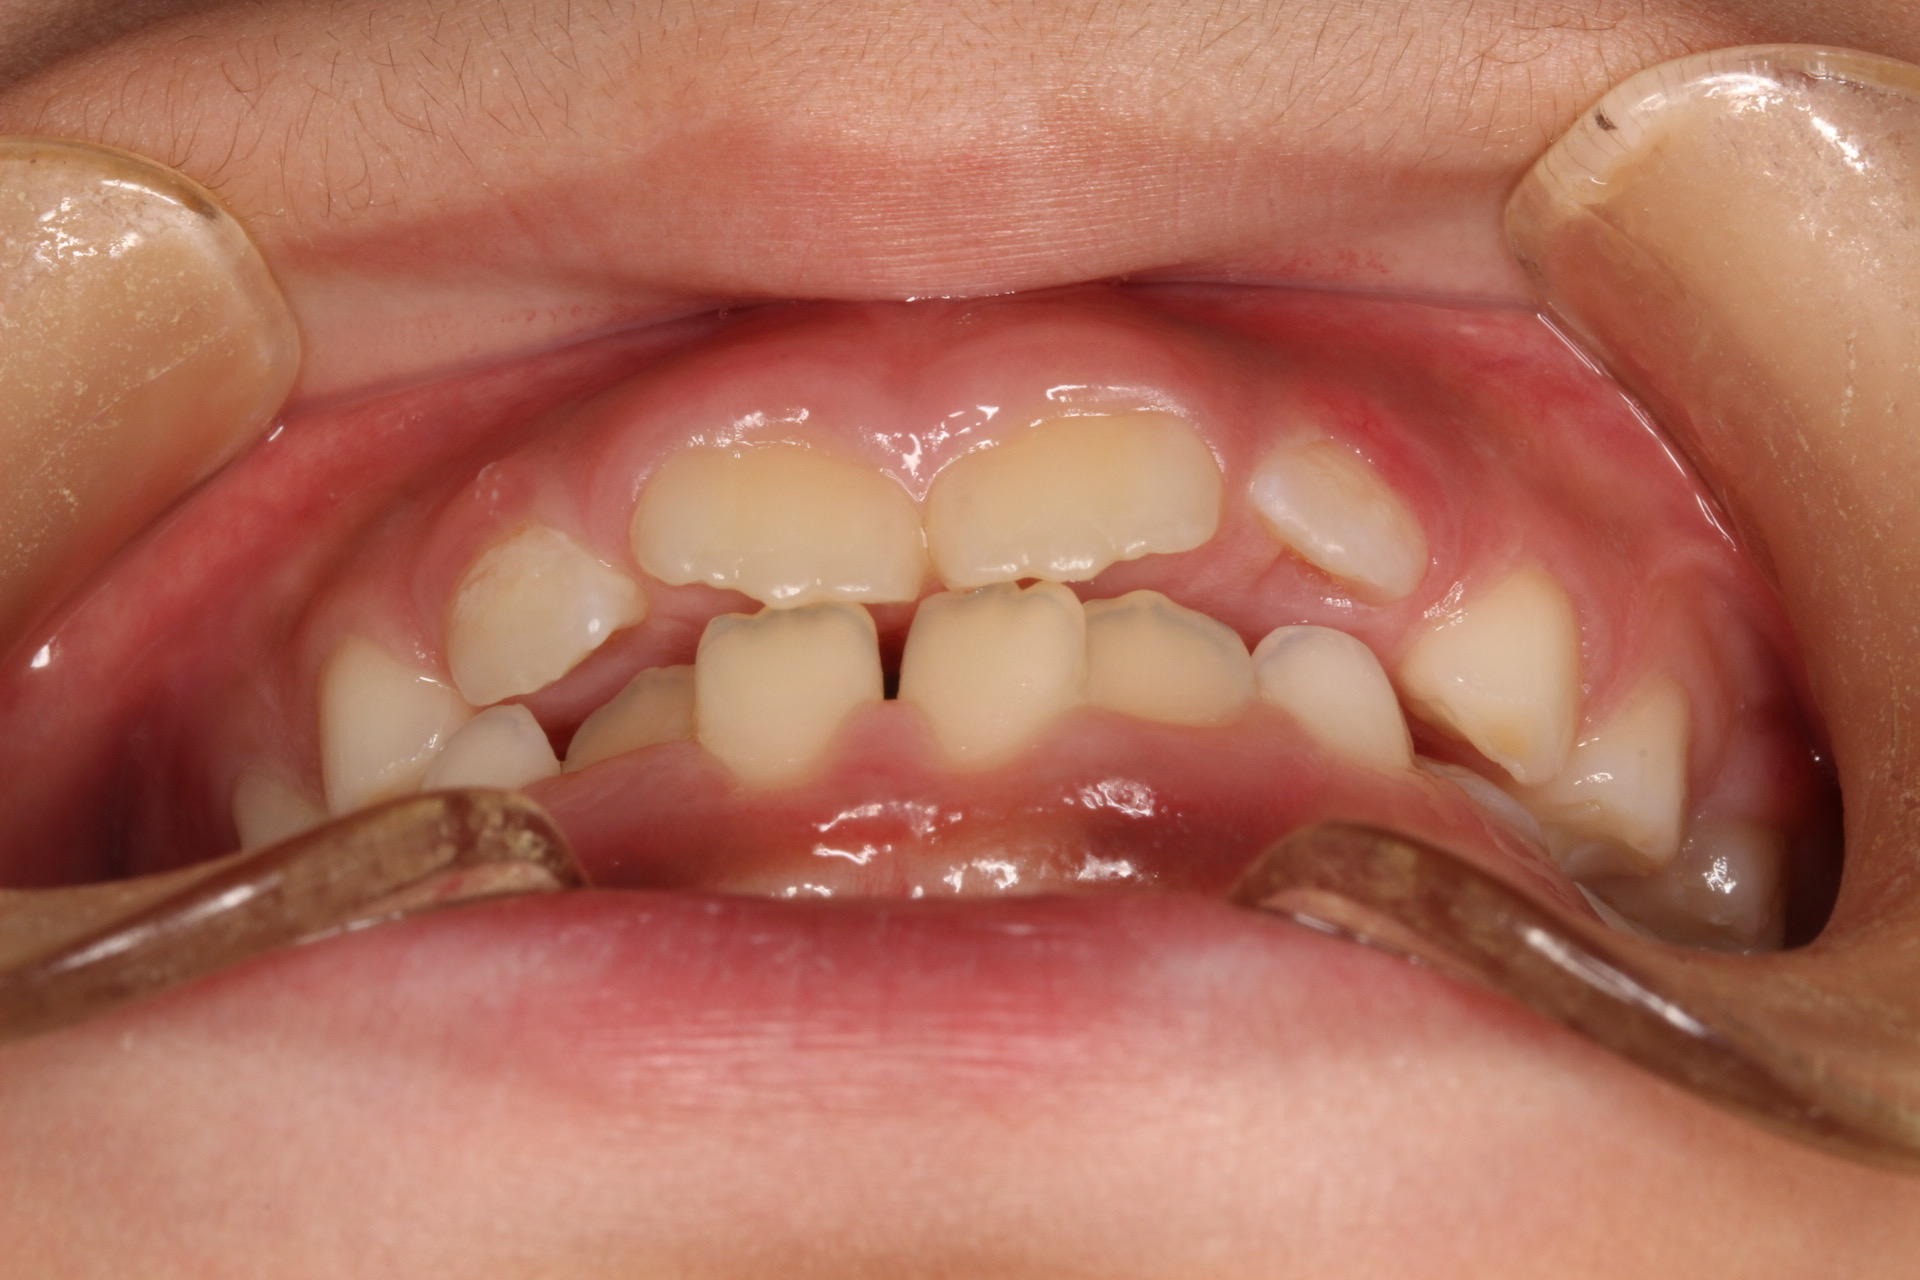

今回ご紹介する患者様は、上下の叢生を気にされており、矯正検査後叢生Ⅰ級(Ⅲ級傾向)と診断いたしました。

矯正術前:正面

| 治療内容 | 患者様は上下の叢生を気にされており、矯正検査後叢生Ⅰ級(Ⅲ級傾向)と診断いたしました。 |